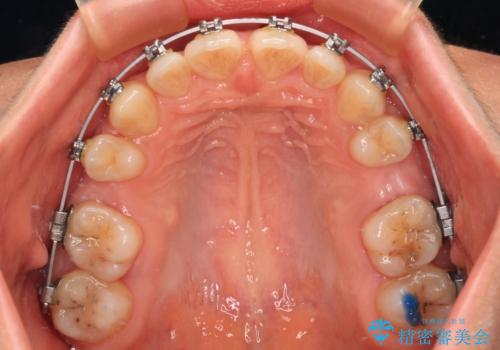

- メタルブラケット

乳歯を残し、欠損部位のスペースを適正な幅に拡大し、インプラント補綴治療により歯列を整える治療も考えられましたが、ご本人から飛び出している前歯をどうしても引っ込めたいとの要望があったため、残存乳歯ならびに上顎左右第二小臼歯を抜歯して、歯列を整えることとしました。

上下臼歯の咬み合わせ改善には補助装置を、深い咬み合わせ改善にはユーティリティーアーチを活用し、ワイヤー装置にて矯正治療を行うこととしました。